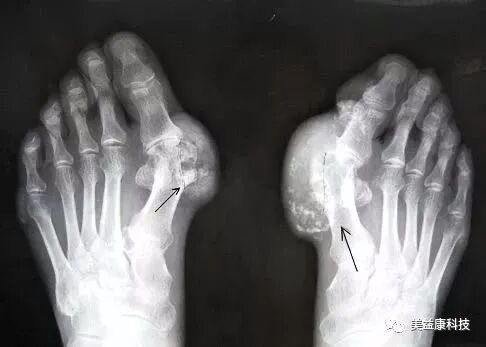

足部X射线平片下的痛风石影像